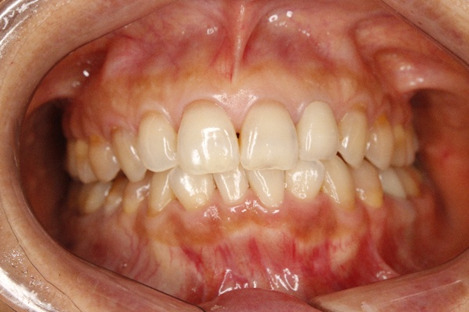

患者様は50代前半の女性で、「くいしばりが気になる」「顔が傾いている」「特に右顎が疲れる」というお悩みを抱えていました。

上の写真のように、治療開始前は「まっすぐ正面を見てください」と言っても、どうしても顔が曲がってしまう状態でした。また、「咬合平面」と呼ばれる上の歯並びのラインが、正面から見ると右下がりになっていました。

一見すると、下の前歯に多少の凸凹があるものの、そんなに目立って歯並びが悪いわけではないので、患者様も噛み合わせに問題があるとは思っていませんでした。

治療後の写真は、以下のとおりです。

噛み合っている面に傾きがなく、床に対して真っすぐになりました。また、「真っすぐ正面を見てください」と伝えたときに、首が曲がらなくなりました。3Dデータを見ても、接触点(緑色と赤色)が全体に分散しました。

患者様いわく、不均衡な筋肉の緊張が取れて、食いしばりも気にならなくなったとのこと。余計な力がかからないので、顎が疲れることもなくなったそうです。顔の傾きは顕著に改善していますね。